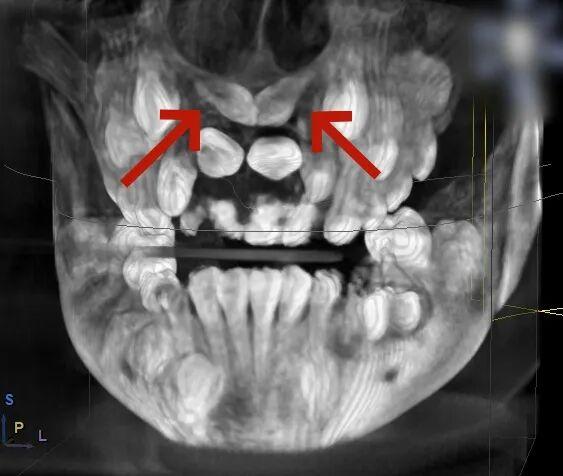

小胡已经9岁了,本该完成换牙的“新门牙”却迟迟没有萌出的迹象。家长带着他来到青岛市妇女儿童医院检查,拍摄X光片后发现,小胡的上颌骨内竟然埋伏着2颗多生牙,这两颗“不速之客”横着长在门牙牙根处,位置高至鼻底,还伴随唇向倾斜,阻碍了恒中切牙的正常萌出。

术前,医生通过 CBCT 扫描获取患者颌骨的精准立体影像,清晰定位埋伏牙的位置、形态以及与周围血管、神经的关系;随后在电脑上进行虚拟手术设计,规划出最佳的拔除路径,巧妙避开重要组织;最后通过3D打印技术,定制出完全贴合患者口腔结构的导板。这块小小的导板,就像是为手术钻头安装了“GPS导航”,能在术中精准引导器械方向,让拔牙过程变得微创、安全、高效。

口腔团队经过全面评估和分析,最终为小胡确定了3D数字化导板引导的手术方案。

牙支持式定位导板